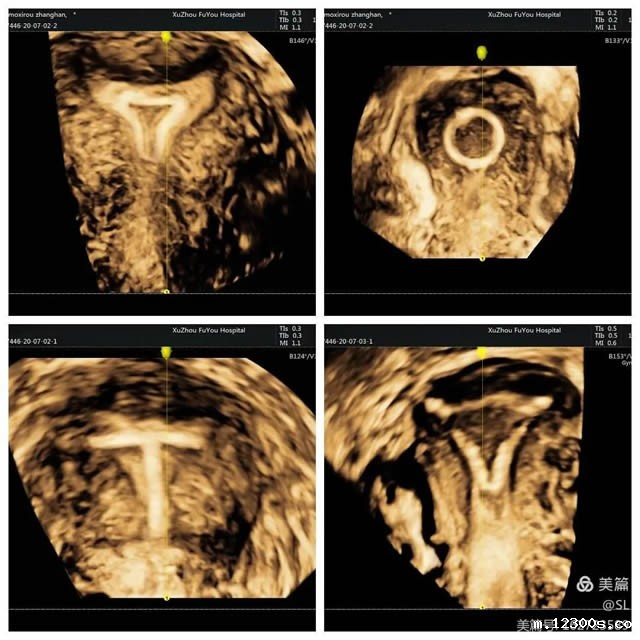

2 精准诊断妇科疾病

先天性子宫畸形是妇科的常见疾病,也是女性不孕不育、习惯性流产、胎儿宫内发育迟缓等疾病的主要原因之一。经阴道三维彩超在评估子宫病变等方面,提供了更丰富的影像信息。这种超声技术不仅能够更好的观察子宫外形轮廓及宫腔内膜的形态,还能清晰观察患者宫腔内的可疑部位和周围组织,帮助医生更准确的分析判断病情。

张丽主任提到,经阴道三维超声是在二维超声基础上技术升级的检查手段。二维超声是断层扫查,很难显示冠状切面,三维超声可以立体实时、从多个面来观察,提供比二维超声更丰富的信息量,因此医生根据三维彩超来诊断,结果会更加准确。

3 精确定位节育器

张丽主任提到,有一位外地患者,因为节育器偏移发生下腹部疼痛,当地卫生院找不准位置取环失败后,连夜转诊到18新利。超声科医生通过三维彩超精准定位,确定了节育器偏移到了子宫肌层,最终顺利取出。

三维彩超的立体成像、图像切割、图像旋转及高平面图像分析功能,能直观、立体显示宫腔的形态结构及其与周边邻近组织的立体关系。因此,清晰显示节育器位置及形状,便于医生操作,也可以大大减少患者的痛苦。